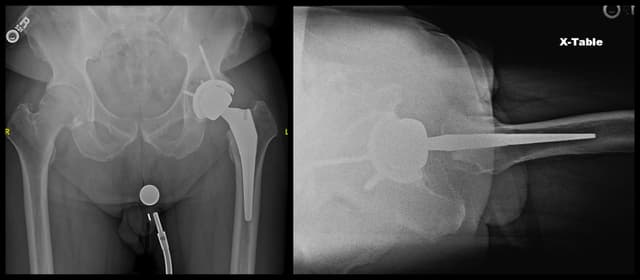

Imaging

Post-op